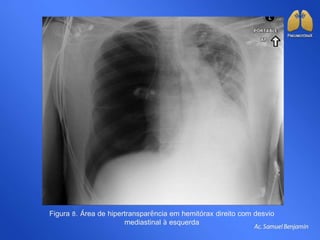

Figura 8. Área de hipertransparência em hemitórax direito com desvio

mediastinal à esquerda

Figura 8. Áreade hipertransparência em hemitórax direito com desvio mediastinal à esquerda